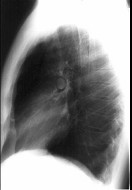

- 单项选择题在哮喘急性发作的病程中患者出现颈部皮下气肿,胸片见图。说明此患者有下列哪一种并发症存在 ( )

A、气胸

B、纵隔气肿

C、间质性肺气肿

D、肺囊肿

E、肺大疱